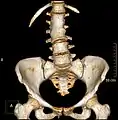

Block vertebrae

Block vertebrae occur when there is improper segmentation of the vertebrae, leading to parts of or the entire vertebrae being fused. The adjacent vertebrae fuse through their intervertebral discs and also through other intervertebral joints so that it can lead to blocking or stretching of the exiting nerve roots from that segment. It may lead to certain neurological problems depending on the severity of the block. It can increase stress on the inferior and the superior intervertebral joints. It can lead to an abnormal angle in the spine, there are certain syndromes associated with block vertebrae; for example, Klippel–Feil syndrome. The sacrum is a normal block vertebra.

Congenital block vertebra in the lumbar spine (partial vertebrae 3 and 4). The rear portion of the disc still exists.

Congenital block vertebra of the lumbar spine. CT volume rendering.